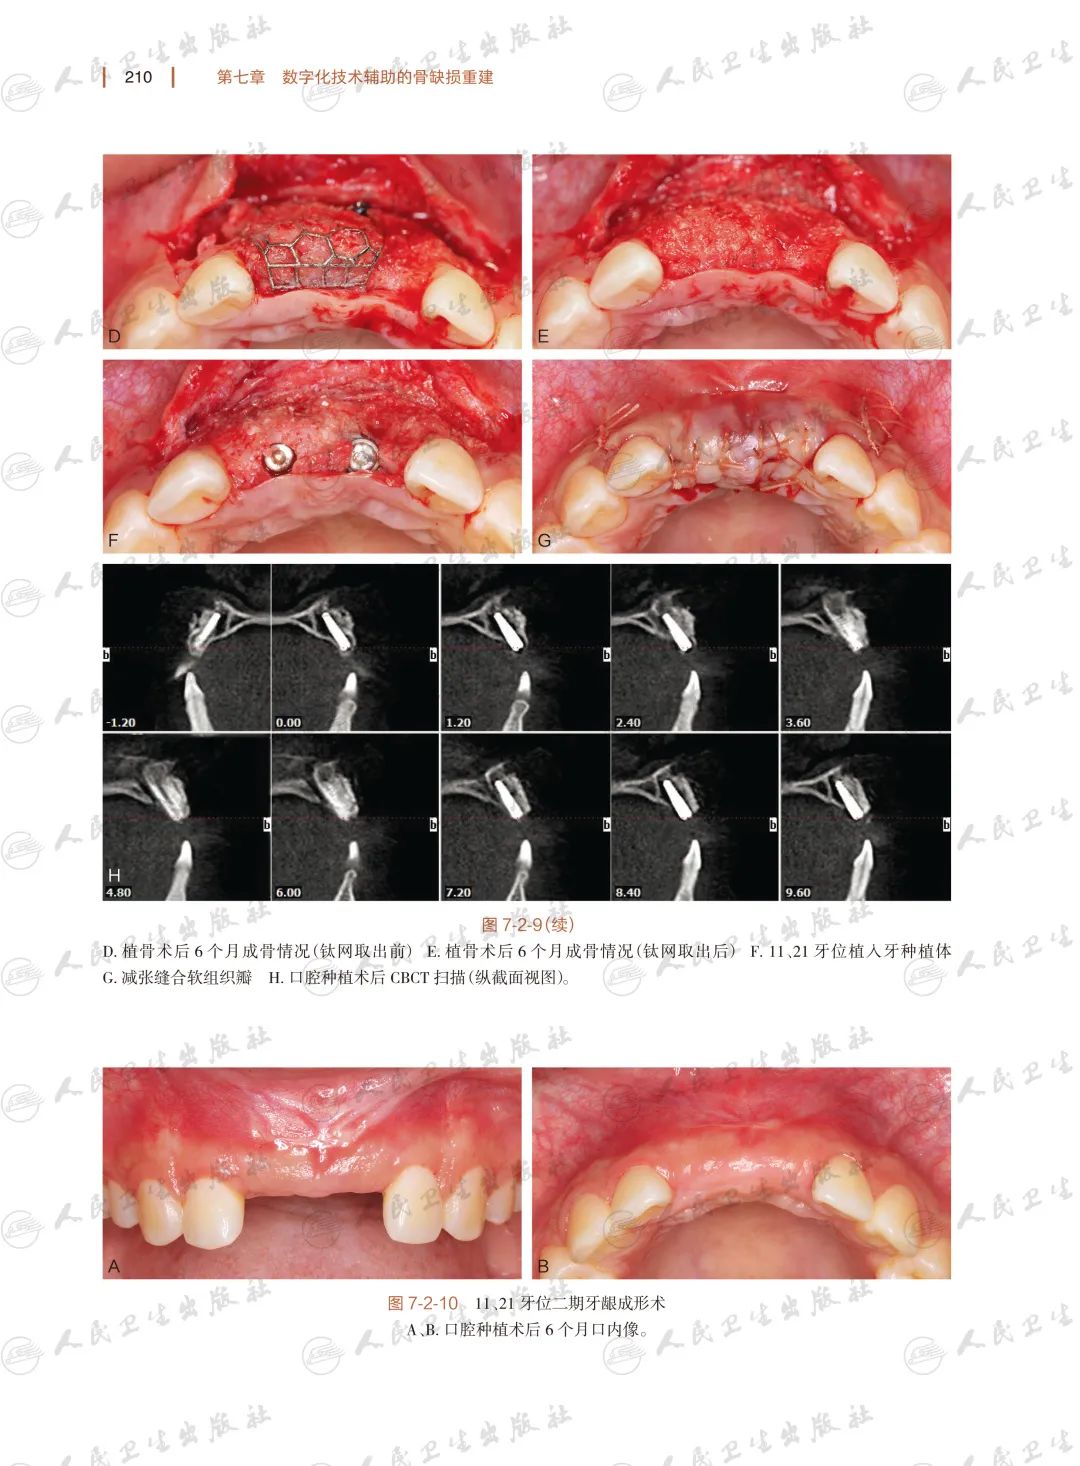

数字化技术在骨缺损重建口腔外科中的应用